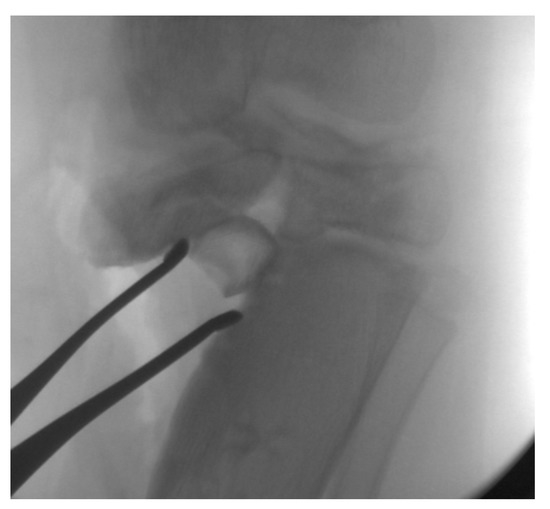

14. Hemi-Plateau Elevation Osteotomy

15. Combined Osteotomies